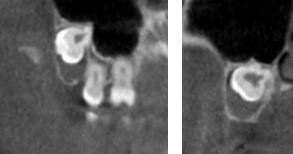

The images below are examples of pathology that have been found over the last year, usually on routine exams. Without Cone beam CT most of the pathology would go unnoticed. Patient names have been removed for privacy. Thank you for allowing the use to educate our patient base on the benefits of this imaging modality.

Case 4: New patient exam uncovered a nasopalatine duct cyst behind the front top teeth going to the premolars. Oral surgeon referral for removal.

Case 8: CBCT is used weekly to evaluate root end abscess of dead, infected and broken teeth.